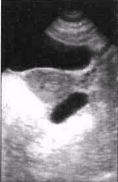

1. Однокамерный вариант

. В пространстве между одним из яичников и маткой (вдоль боковой стенкиматки), то есть в одной из параметральных областей, выявляется жидкостное образование правильной вытянутой формы со значительным преобладанием продольного размера над поперечным. При этом конфигурация патологического очага может быть овальной (рис.1), веретенообразной или S-образной. Структура жидкого содержимого однородная. Матка, эндометрий и яичники не изменены. На стороне поражения почти всегда лоцируется неизмененный яичник. Оптимальные условия для визуализации патологического очага создаются при поперечном обзорном сканировании с использованием способа дозированной компрессии передней брюшной стенки УЗ-датчиком (желательно секторным).

Как правило, этот вариант воспаления маточных труб встречается у молодых женщин и часто обнаруживается при первичном обращении к гинекологу.